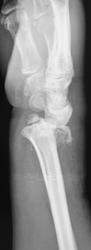

Сегодня был контроль, однако желаемое не достигнуто...

А "банкротом" может оказаться пациентка... Но это уже лирика)). Наше дело в данном случае маленькое: ДИНАМИКИ НЕТ, ВЫВИХ НЕ УСТРАНЕН. И всё))